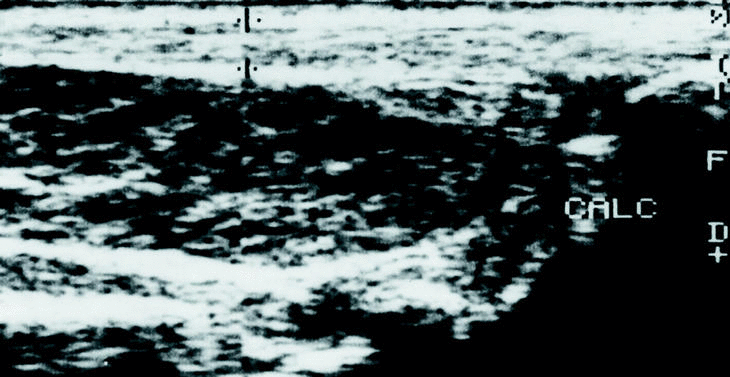

Desde 1990, se han identificado en el Servicio de Cirugía Ortopédica y Traumatología del Hospital USP-Santa Teresa de La Coruña 10 casos de músculos sóleos accesorios en 7 pacientes (tres casos bilaterales). Se trataba de 4 hombres y 3 mujeres, con una media de edad de 25 años (mínima: 4 y máxima: 42 años). En 6 casos, los pacientes acudieron a la consulta por presentar dolor en la zona aquílea durante el ejercicio físico, identificándose otros 2 casos al examinar el lado contralateral y un caso bilateral (el niño de 4 años) acudió a consulta porque sus padres estaban inquietos entre el aspecto de las regiones retromaleolares tibiales. En la exploración física se apreciaba en todos los casos, una tumoración retromaleolar interna del tobillo (fig. 1), ocasionalmente sensible a la palpación y que provocaba molestias con los ejercicios de estiramiento selectivo del sóleo en aquellos casos previamente sintomáticos; el tendón de Aquiles aparecía de grosor normal y sin nódulos en su interior en todos los casos. En los casos en que se realizó un estudio radiográfico, se podía apreciar una obliteración del triángulo de Käger (grasa preaquílea) por una masa de partes blandas (fig. 2). En todos los casos, se realizó un estudio ecográfico en el que se confirmó la existencia de una masa preaquílea, bien delimitada, con una ecogenicidad similar a la del músculo estriado, que finalizaba a una distancia variable del calcáneo dependiendo de su tamaño (fig. 3). En los 2 primeros casos, se realizó además un estudio de RM para confirmar el diagnóstico de músculo sóleo accesorio (fig. 4). Tras el diagnóstico, se instauró un régimen de estiramiento selectivo del sóleo y reducción del nivel de actividad física hasta la desaparición de la sintomatología, seguida de la reincorporación progresiva a la actividad previa por debajo del nivel de molestia, hasta la normalización de los pacientes. En todos los casos menos uno (el paciente de más edad) fue posible retomar la actividad física sin limitaciones; en éste último caso, el paciente se encuentra subjetivamente mejor, aunque persiste el dolor al correr más de 15 a 20 minutos, por lo que se encuentra a la espera de decidirse a realizar una fasciotomía del sóleo accesorio.

Figura 3. Ecografía de un paciente portador de un músculo sóleo accesorio en la que se puede apreciar la existencia de un vientre muscular ocupando el espacio preaquíleo (el tendón de Aquiles está delimitado por las 2 +; calc: calcáneo).